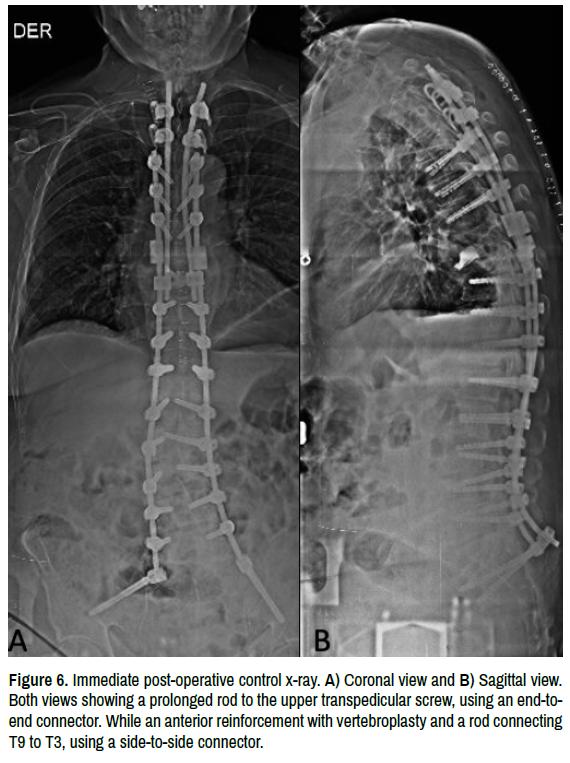

A 75-year-old male with history of medically controlled AH and PD, with low-back-pain radiating to both limbs, predominantly to the left. Tendency to a positive balance gait and left coronal deviation. X-rays showed a degenerative lumbar scoliosis with 40o of Cobb angle (Figure 1). Underwent a posterior spine fusion from T9 to Iliac bones, plus lumbar stenosis decompression. Postoperative x-rays and clinical evaluation were successful (Figure 2). After six weeks, he was in great pain localized in thoracic spine due to movement, and x-ray control showed a fracture of the Upper Instrumented Vertebra (UIV) with Regional Kyphosis Angle (RKA) of 30.6o (Figure 3). Due to multimorbidity, treatment choice was conservative with analgesic medication and Taylor Brace. After three months, still with thoracic pain. Supine x-ray with RKA of 23.2o, and standing x-ray RKA of 46.3o (Figure 4); patient was not agree for a revision surgery, so we continued with conservative treatment. Four months after surgery was performed a computed tomography (CT), with a 75% lysis of T9 and inferior platform of T8 affected (Figure 5). After five months from the first surgery, patient accepted a revision surgery. Extension of instrumentation was performed by the following way: removed of T9 screws, transpedicular screw were placed in T7, T6 and T5; transverse process hooks were used in T4 and T3. Due to a bone cavity, a vertebroplasty was performed in T9 for anterior stability. The length of the previous rod was extended, using an endto- end connector to the most cephalad segment where transpedicular screw were placed, and a reinforcement rod to the vertebroplasty using a side-to-side connector between T9 to T3 (Figure 6). After six weeks of surgical treatment, patient with an adequate clinical and radiological outcome.

Figure 6. Immediate post-operative control x-ray. A) Coronal view and B) Sagittal view. Both views showing a prolonged rod to the upper transpedicular screw, using an end-toend connector. While an anterior reinforcement with vertebroplasty and a rod connecting T9 to T3, using a side-to-side connector.